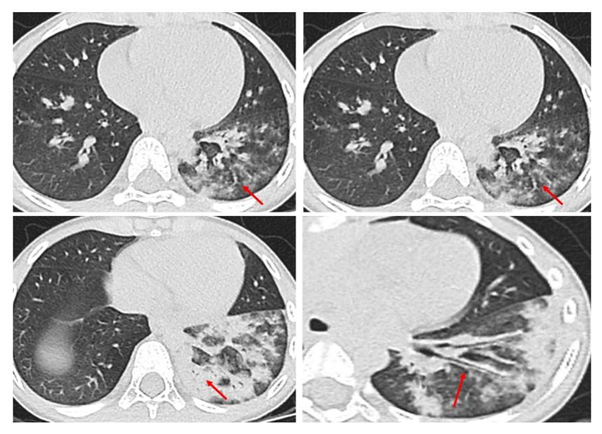

影像学检查尤其是CT是重要的检查手段,也是临床判断病情严重程度和评估预后的主要依据之一。支原体肺炎病理变化是首先侵犯气道粘膜上皮,引起支气管壁水肿增厚,接着向气道周围间质蔓延,引起肺间质充血、水肿及炎性细胞浸润,最后延伸至肺泡。在CT图像上主要有以下几种表现:

1.支气管壁增厚:支气管肺炎较可靠征象,支气管壁光滑、均匀增厚,可侵犯周围间质,周围边缘模糊,表现为支气管炎及周围炎,多由肺门向外周进展。

2.树芽征:细支气管或终末支气管内粘液阻塞,远端增粗,像树上发的新芽。

3.树雾征:支气管周围间质水肿,形成沿支气管蔓延的磨玻璃影,如同树周围的雾一样。

4.磨玻璃影:间质内水肿或部分肺泡内渗出,表现为磨玻璃样影。

5.大片实变:表现为中-高密度阴影,可有支气管气象,可伴有肺不张及胸腔积液,早期可表现为小叶中心结节影,随着病灶进展,进展为全小叶或更大范围。

随诊疾病的不同阶段,多种形态、大小不等和密度不均的病灶可混合出现,支气管壁增厚、树芽征、树雾征及实变影等征象可同时存在,结合咳嗽、发热等症状,可对支原体肺炎做出诊断。